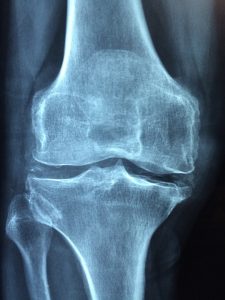

determine what further actions need to be taken. At

, you should see a doctor. They can see what’s going on by doing an examination of your injury; taking x-rays in many cases or recommending MRI’s along with reviewing your medical history. For prevention and care please contact the Millennium medical center near you. Have your boy or girl had their sports physical yet? In order to play any sport in school, having a